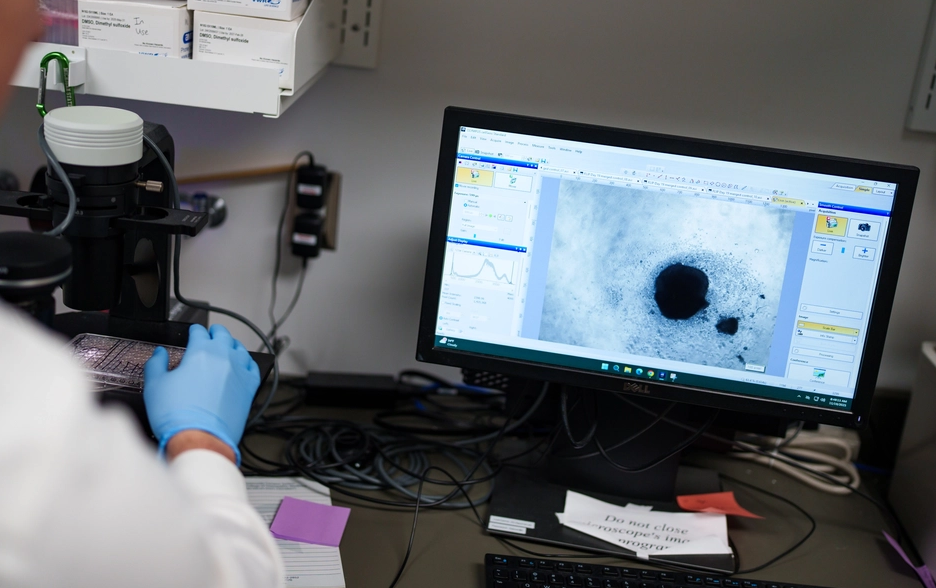

人類細胞核內染色體詳細圖譜發布